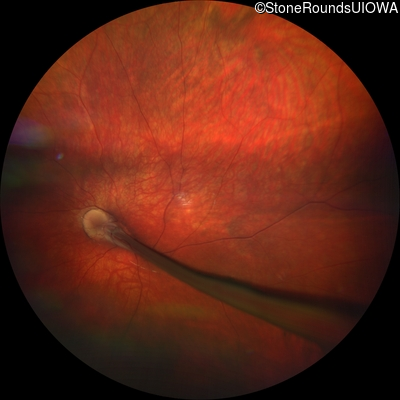

Visit at age: 23 months

Fundus Photography - Right - UCUSUM

Exemplar